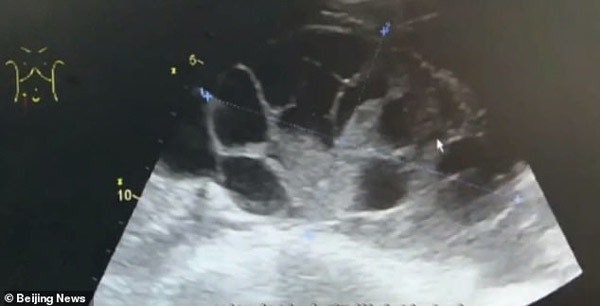

Ba ngày sau khi phẫu thuật, sức khỏe nữ sinh nhanh chóng xấu đi, cô bị đầy hơi nghiêm trọng, khó thở và nhanh chóng được đưa đến bệnh viện. Qua kết quả kiểm tra, nữ sinh được chẩn đoán mắc hội chứng quá kích buồng trứng, một tình trạng xảy ra khi buồng trứng trở nên quá kích thích do sự phát triển của trứng và chất lỏng tích tụ xung quanh.

Cô gái trẻ được cho là đã tiêm hơn 10 mũi kích thích rụng trứng trước khi phẫu thuật lấy trứng. Các bác sĩ tiết lộ rằng hơn 5 lít chất lỏng đã được rút ra từ bụng của cô. Rõ ràng, buồng trứng của cô đã bị mở rộng như thể mang thai 7-8 tháng.

Theo các bác sĩ khoa sinh sản, nếu muốn lấy trứng, bác sĩ phải dùng một cây kim phẫu thuật đầu rỗng, đâm thủng nang buồng trứng đang ở giai đoạn chín muồi mới lấy được ra. Nhưng thao tác này cần đến những người có tay nghề chuyên nghiệp, nếu rơi vào tay những người không được đào tạo bài bản, sẽ phải chịu di chứng như tràn dịch màng phổi, buồng trứng bị quá kích, nặng hơn là vô sinh, thậm chí nhiễm trùng, dẫn đến tử vong.